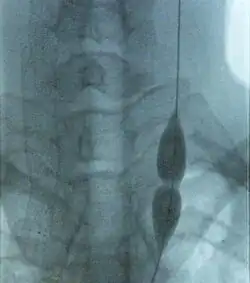

Balloon dilatation of stenosed jugular vein in a MS patient. Stenosis prevents the balloon from inflating (in the middle) while pressure is low.

Further trials are required to determine if the benefits, if any, of the procedure outweigh its risks.[22] Most experts, and medical and patients organizations, including the National Multiple Sclerosis Society of the USA or the Cardiovascular and Interventional Radiological Society of Europe (CIRSE), recommend not using the proposed treatment outside clinical trials until its effectiveness is confirmed by controlled studies.[3][5][7][22][38][39] Moreover, the CIRSE has stated that treatment research should begin by a small, placebo-controlled, prospective randomised trial which should be monitored by an independent organization.[39] An exception has been the Society of Interventional Radiology in the US and Canada, which considered research on the effectiveness of CCSVI intervention to be inconclusive as of 2010.[40] In March 2013 a press release indicated that the first prospective, placebo-controlled study of balloon angioplasty for MS had not shown any benefit of the therapy. The study, a phase II clinical trial designed to evaluate safety and efficacy of endovascular treatment, enrolled initially 10 patients that received the treatment and 20 more afterwards that were either allocated to receive angioplasty or a placebo intervention.[41]

Balloon angioplasty and stenting have been proposed as treatment options for CCSVI in MS. The proposed treatment has been termed "liberation therapy" though the name has been criticized for suggesting unrealistic results.[14]

Balloon angioplasty in a preliminary, uncontrolled, unblinded study by Zamboni improved symptoms in MS in a minority of treated people.[44] Although the procedure pushes the vein open temporarily, the effect does not persist,[22] supporters advise against using stents.[45]

Venous percutaneous transluminal angioplasty (PTA) has proven to be safe but due to its ineffectiveness is not recommended.[15]